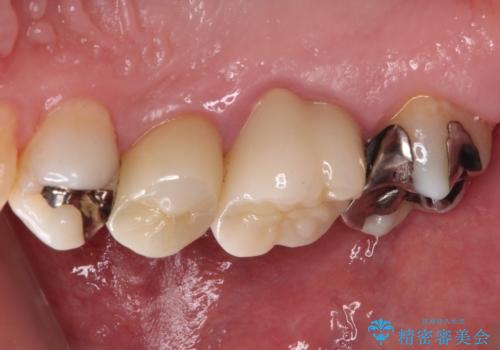

根管治療を行った後にオールセラミッククラウンにて補綴することとしました。

小臼歯は根管治療後に痛みが引きましたが、隣の大臼歯の痛みは引かなかったため、大臼歯も根管治療を行いました。

根管治療後に痛みは引き、半年後のレントゲン写真では根尖の病変の消失が認められました。